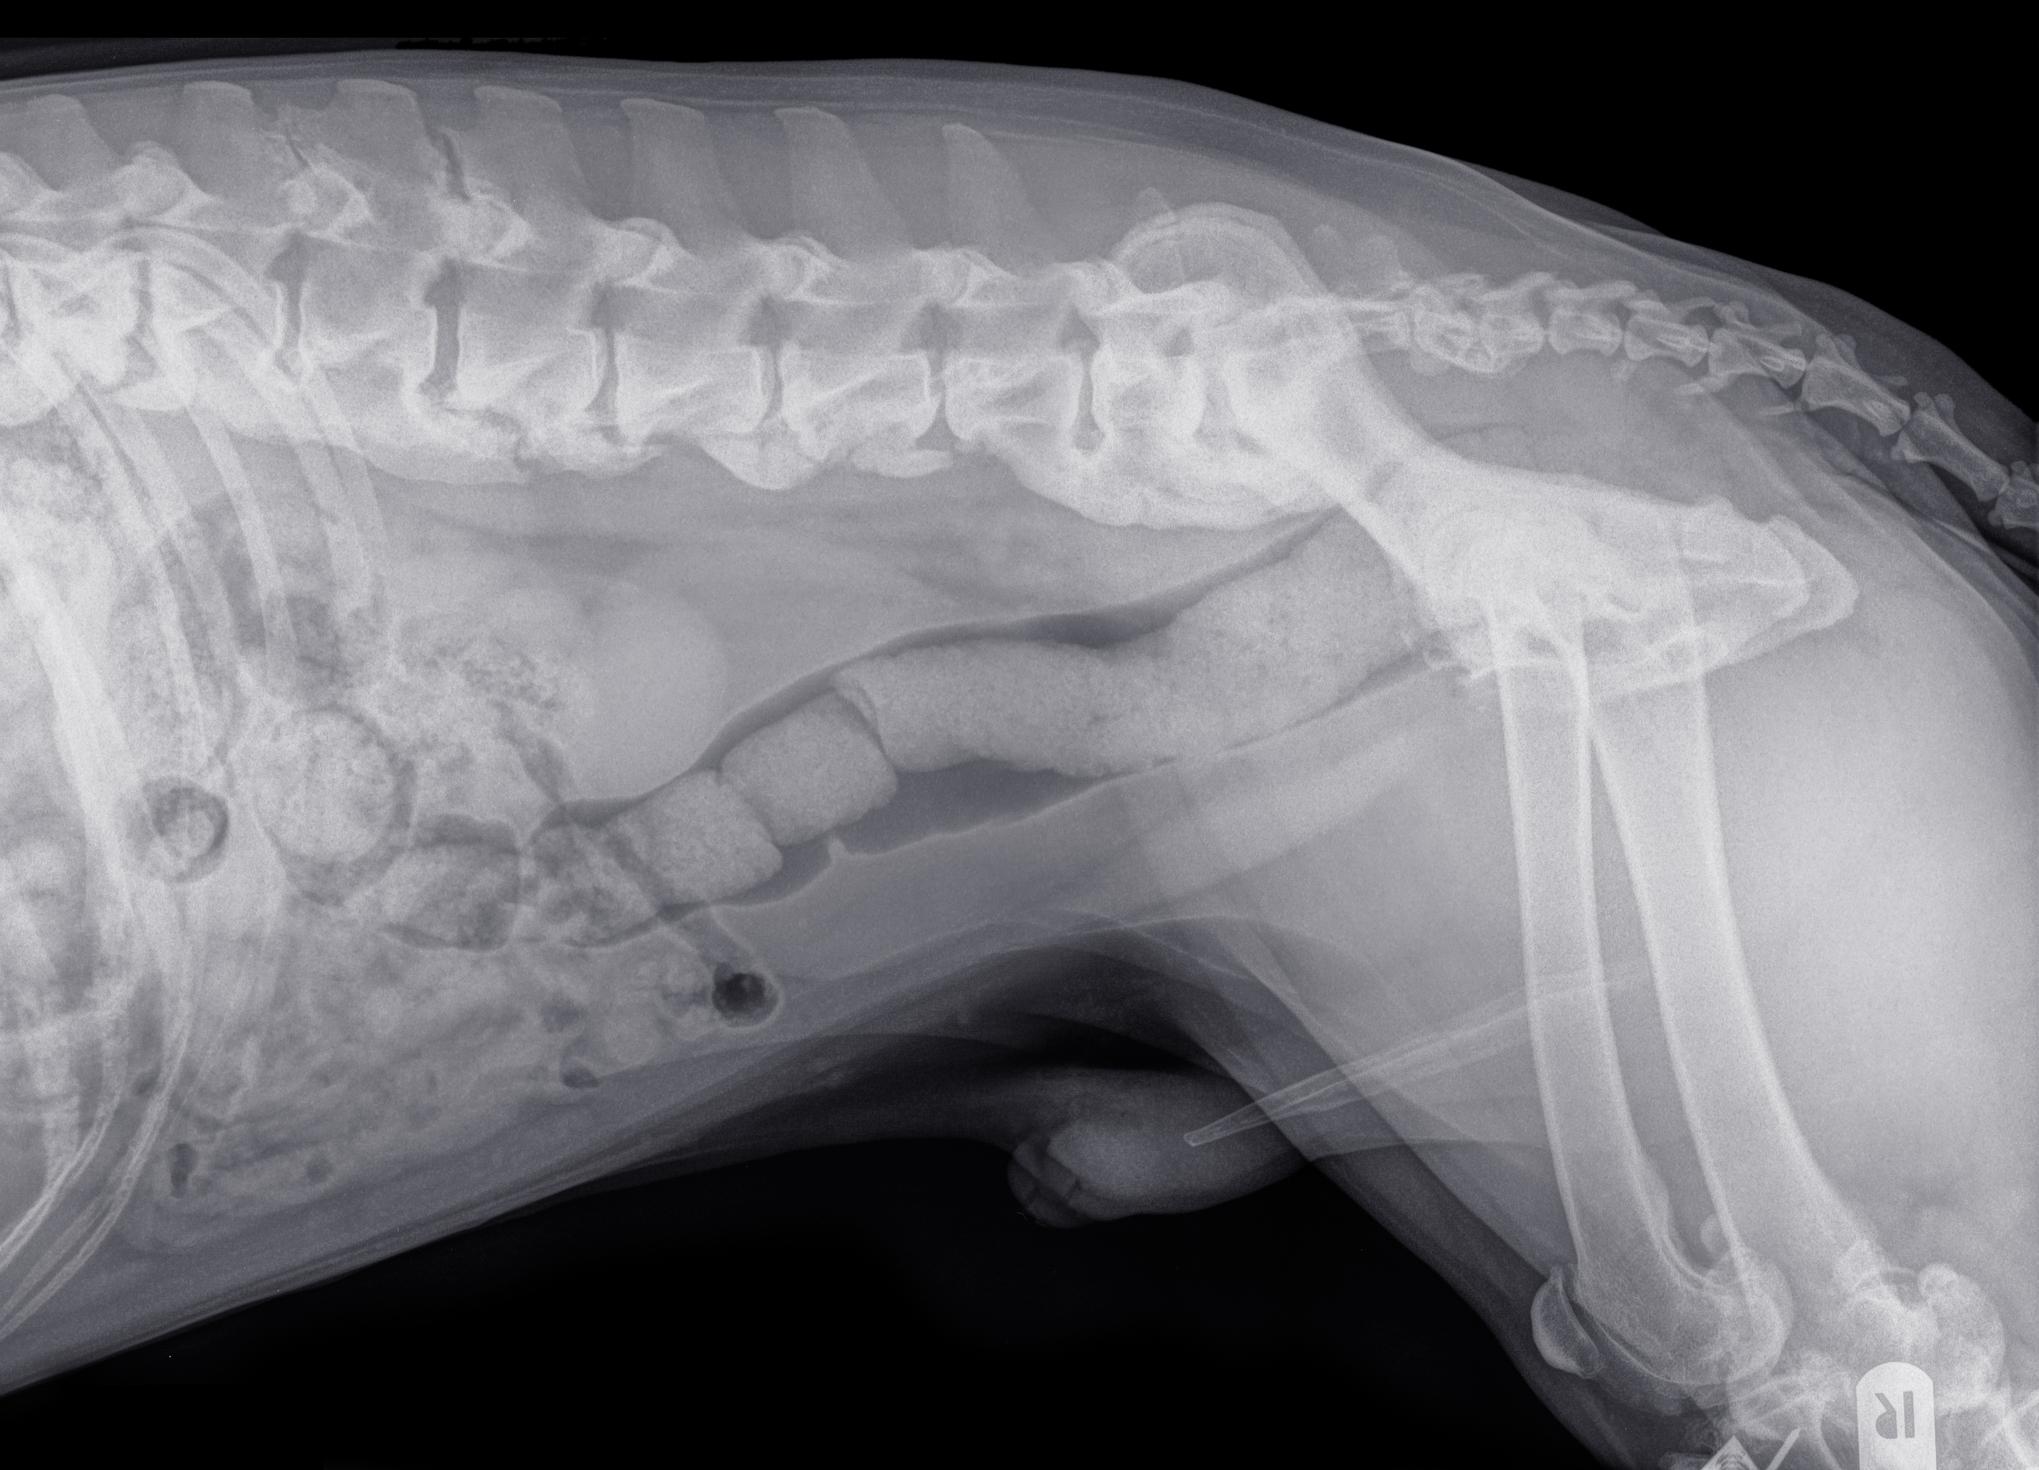

En la exploración radiográfica, la espondilosis se observa en forma de protrusiones (osteofitos) del borde inferior de las vértebras hacia los extremos anterior y posterior de las vértebras adyacentes. A medida que progresa, adquiere un aspecto en forma de gancho que comúnmente recibe el nombre de “pico de loro”. En los casos más avanzados, se llega a formar un puente que une los cuerpos de las vértebras a nivel ventral. Cuando únicamente se observa un osteofito aislado en una vértebra, se suele hablar de espondiloartrosis canina.